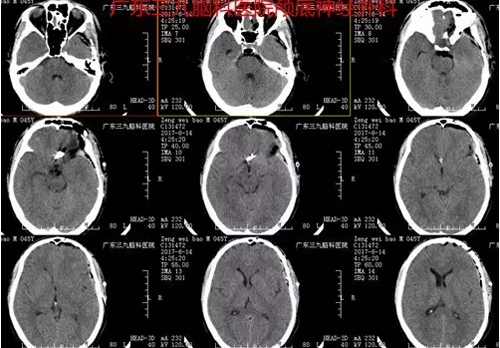

患者曾某,男,45岁。因无明显诱因头痛于6月13日入院,当地医院CTA提示:蛛网膜下腔出血,前交通动脉瘤。入院后完善术前相关检查,6月14日全麻下行“前交通动脉瘤夹闭术”,术程顺利,术后恢复良好。术后诊断:前交通不规则囊状动脉瘤。

图6:术后CT呈术后改变,术区高密度影处为动脉瘤夹,术区未见出血